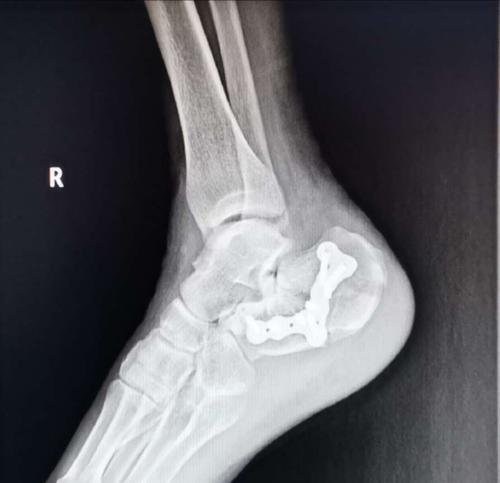

跟骨骨折大l切口内固定